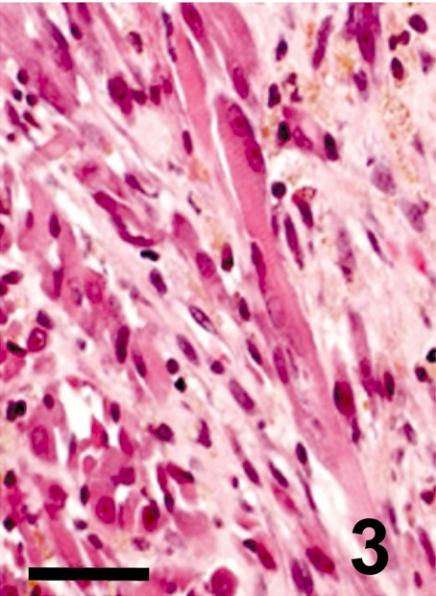

A rhabdomyosarcoma arising in the larynx of a dog.

A neoplastic nodular lesion, 2 × 3 cm in diameter, was found in the larynx of a 6-year-old spayed female dog. The tumor was ill-circumscribed, consisting histologically of large round cells with abundant cytoplasm interspersed with small round cells with less cytoplasm and occasional multinucleated cells (myotubes). Immunohistochemically, tumor cells were positive for myoglobin, desmin and vimentin in varying degrees, but negative for S-100 protein, GFAP or cytokeratin. Cytoplasmic myofilaments/myofibrils with a dense Z-line-like structure were seen, the fine structures of which were complemented by PTAH stain. Based on these findings, the tumor was diagnosed as a rhabdomyosarcoma, a very rare tumor in the larynx of dogs.